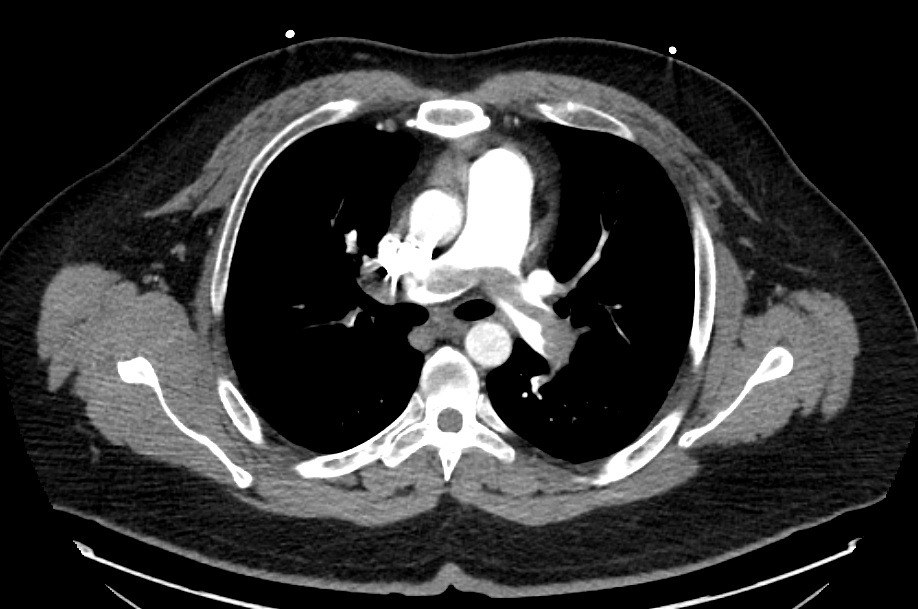

Repeat CTA (poor contrast bolus timing) persistent saddle PE

! Anyone has seen this? Despite tPA. persistent RVdilated reason for above EKG! @Yalecards @infeldMD @turilrh @jedicath @mirvatalasnag @jgloyo @PowellJose @karimratib @KHERA_MD @RealKushAgrawal @shiskumar33 @samikhan0

We went ahead and did CAT12 @PenVascular lightening embolectomy. It felt like tissue that’s why TPA failed! Patient did well!